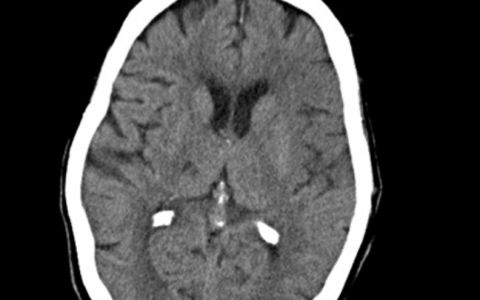

A 34-year-old woman with a medical history significant for tobacco(烟草) and cocaine(可卡因) abuse is brought to the emergency department (ED) by a family member after a witnessed seizure. She is currently unarousable. Vital signs are: blood pressure 198/100 mm Hg, heart rate 62 beats/min, respiratory rate 8 breaths/min. Glasgow Coma Scale score is 6. She is immediately intubated and elicits bilateral extensor motor responses with bilateral dilated pupils at 5 mm. The ED physician decides to mechanically ventilate to hyperventilate her, and administers a dose of IV mannitol 25%. CT is shown below.

该患者患有急性梗阻性脑积水伴累及第四脑室的脑室内出血,可能与可卡因滥用有关。她将受益于通过脑室外引流进行的紧急脑脊液引流。在脑出血的回顾性观察性研究中研究了抗癫痫药物的作用,在这种情况下可能无法挽救她的生命。最后,类固醇和IV组织型纤溶酶原激活剂在继发于脑内出血或脑室内出血的急性脑积水的治疗中没有作用。

D